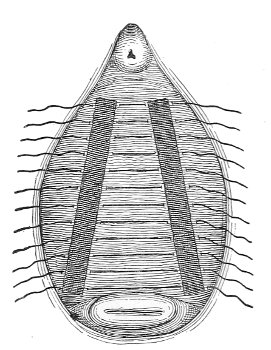

The Vaginal Speculum.—The speculum is an instrument through which a visual examination is made of the vagina, the external os uteri, and the vaginal cervix. A 29 great number of specula have been invented. At the present day the best two instruments of this class are the bivalve speculum, such as Goodell’s (Fig. 6), and the duck-bill speculum (Fig. 7), or perineal retractor, invented by Sims.

Fig. 7.—Sims’ speculum.

The Sims speculum enables us to make the most thorough inspection of the vagina, the vaginal vault, and the vaginal cervix. The Sims speculum is merely a hook or retractor for the perineum, and may be introduced with the woman in the dorsal position, the Sims position, or the genu-pectoral position. If the Sims speculum is introduced in the dorso-sacral position, it is necessary to hold forward the anterior vaginal wall in order to obtain a view of the cervix.

Fig. 10.—The Sims position.

The Sims position, which is also called the latero-abdominal position, is shown in Fig. 10. The woman is placed on the bed or table upon her left side. The side of the face is upon the pillow; the left arm is behind the back, so that the left breast rests upon the table. The thighs are flexed upon the abdomen at an angle of about 90° to the trunk. The right thigh is more flexed than the left, so that the right knee may touch the table above the left knee. The legs are flexed on the thighs. In this position there is a tendency for the intestines, following the force of gravity, to fall from the pelvis, 32 and for the uterus and other pelvic viscera to be drawn up. When the perineum is retracted with the blade of the Sims speculum, air will enter the vagina and the vaginal slit will become distended (Fig. 11). To facilitate inspection of the cervix it is usually necessary also to push forward the anterior abdominal wall by some kind of depressor, such as the one shown in Fig. 8.

Fig. 11.—The cervix uteri exposed with the Sims speculum.

The Sims speculum, with the woman in the dorsal, the Sims, or the knee-chest position, is the most useful instrument by which to expose the cervix uteri for any of the minor operations of gynecology. The manipulations of the operator are not hampered by working between metal walls.